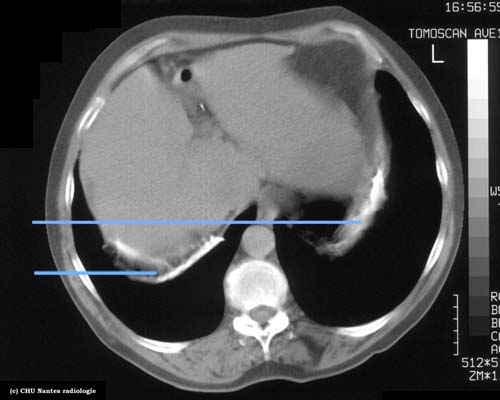

Calcifications pleurales (B)

coupe TDM en fenêtre médiastinale

calcifications pleurales des coupoles diaphragmatiques (coupe  tangente aux coupoles )